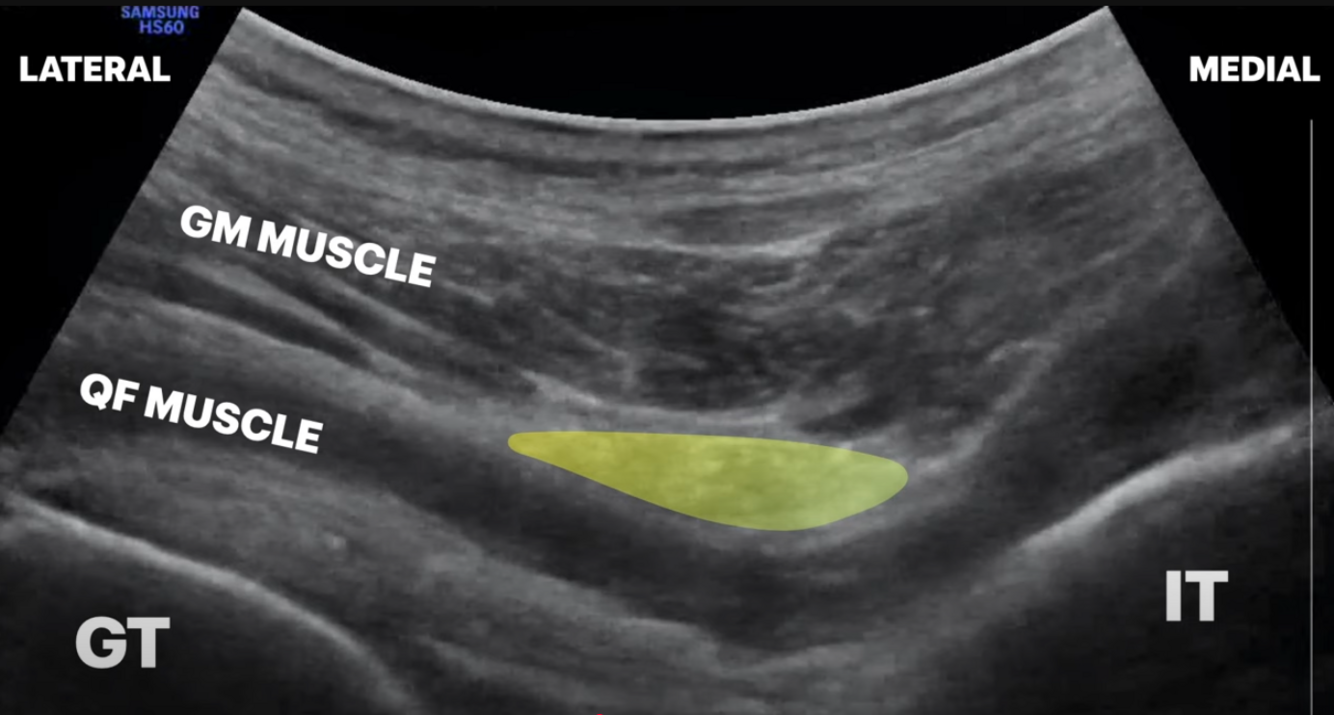

Subgluteal Sciatic nerve

A

PCFN block not guaranteed but can block in same region

Inferior gluteal artery good landmark for plane

Hip flex